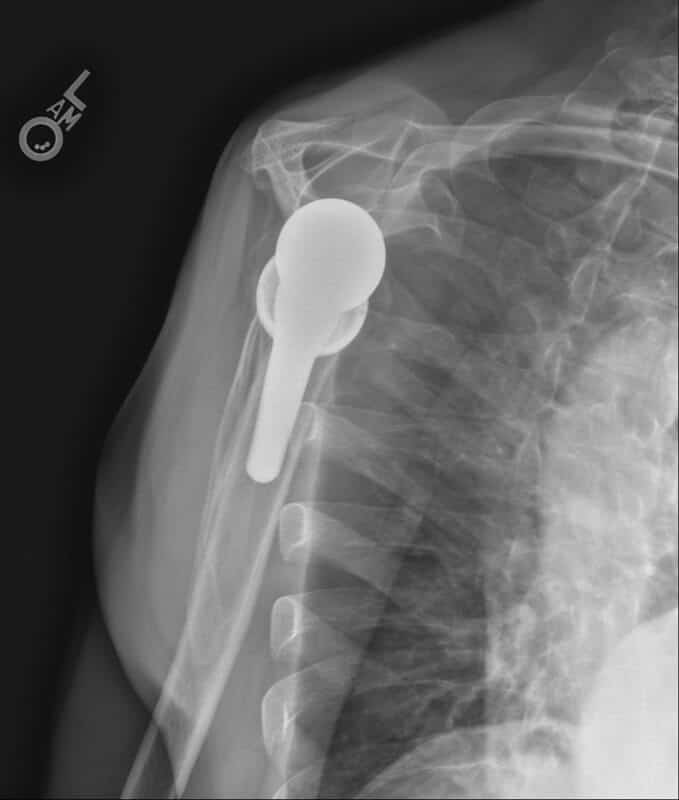

Stryker/Wright/Tornier, Flex Ascend Humerus, Perform Full Wedge Glenoid